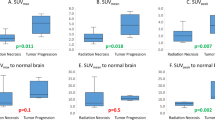

About 113 surgical samples were collected from 14 resected lesions in 12 patients (8 ± 4 per lesion; weighing 0.16 ± 0.12 g). Exactly 10 out of 14 lesions (in 10 out of 12 patients) were positive for tumor recurrence, whereas the remaining 4 out of 14 lesions were negative. In ten lesions positive for tumor recurrence, 76 ± 34% of samples were positive (range, 9–100%). In total, evidence of viable tumor was present on 69 samples (61%), while 83 (76%) had necrosis, with 57 samples (53%) containing both. About 58 samples (55%) were positive for vascular proliferation, 61 (55%) had gliosis, and 45 (41%) had inflammation (not all 113 samples were scored for all). Mean tumor and necrosis content, averaged over all samples from the same lesion, were 29% ± 27% (range, 0–80%) and 23% ± 17% (range, 0–42%), respectively. Mean semiquantitative values for microvascular proliferation, mononuclear and polymorphonuclear inflammatory infiltrates, and reactive gliosis (scale between 0 and 3) were 0.5 ± 0.4, 0.6 ± 0.7, and 0.5 ± 0.4, respectively. Surgical samples with viable tumor had higher 18F-fluorocholine uptake than those without tumor (SUV of 4.5 ± 3.7 compared to 2.6 ± 3.0; p = 0.01). The analysis with a linear mixed model revealed that 18F-fluorocholine uptake in the surgical samples was driven by the degree of reactive gliosis (p = 0.011) and inflammation (p = 0.021); a multivariate regression analysis showed a significant correlation between resection tissue 18F-Fluorocholine SUV and reactive gliosis (p = 0.011), viable tumor (p = 0.015), and inflammation (p = 0.022). No correlation of 18F-fluorocholine uptake with proliferation and percentage necrosis was observed based on both analyses. There was no significant correlation between 18F-Fluorocholine SUV and sample processing time post-injection (r = 0.07) or sample net weight (r = 0.08).

18F-Fluorocholine SUVmax as a function of follow-up time is presented in Fig. 3A (date of last follow-up: October 7, 2019). The data was split into two groups according to median 18F-fluorocholine SUVmax value of 6. Survival distributions were visualized with Kaplan-Meier estimators (Fig. 3B). Patients with 18F-Fluorocholine SUVmax above the median value of 6 had worse prognosis; however, significance was not reached (log-rank test, p = 0.068). Observations were censored if the patient was alive at the time of last follow-up (blue diamonds on Fig. 3A) or deceased from cause other than progressing brain metastases (orange square on Fig. 3A).